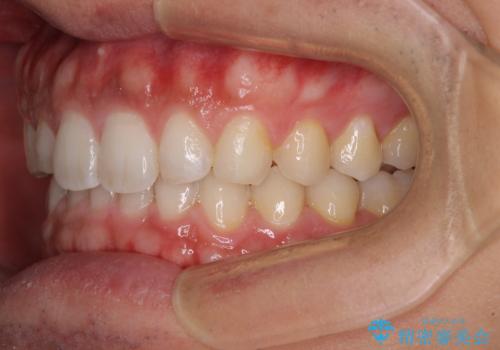

細かい隙間にものがはさまる インビザラインによる矯正治療

- 上下の前歯の隙間を気にして来院された患者様です。

インビザラインを用い、上下歯列のスペースを閉じていくこととしました。